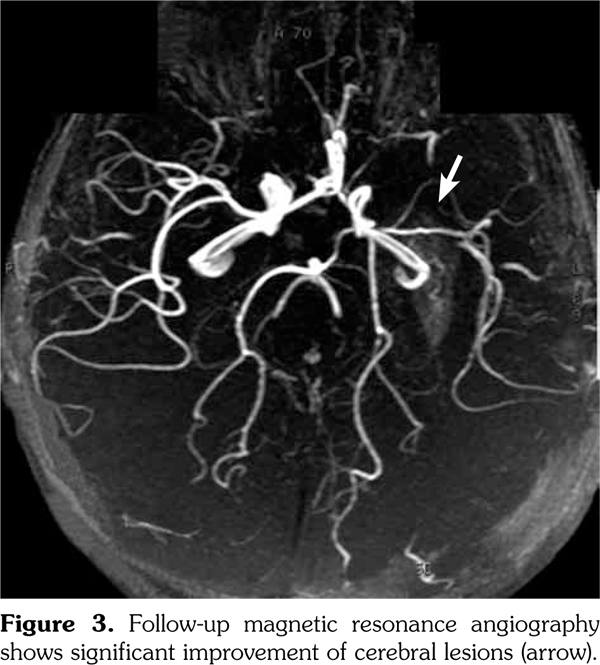

Based on these clinical findings, the patient was diagnosed as HSP, and the skin biopsy showed leukocytoclastic vasculitis with histopathologic evidence of immunoglobulin (Ig) A and M deposition based on direct immunofluorescence staining. A written informed consent was obtained from the parent of patient. The patient was being followed-up as an out-patient. On the 15th day of his follow-up, he admitted to the emergency department by sudden focal tonic- clonic convulsions and unconsciousness. He was not able to use his right hand and foot, also he could not talk. His blood pressure was 105/70 mmHg. Fundoscopic examination was unremarkable. The physical examination showed aphasia, right sided central facial paralysis, and hemiplegia on the right. Deep tendon reflexes were exaggerated and there was extensor plantar response on the right side. Cerebellar functions and sensory testing were normal. In acute laboratory evaluation, serum electrolytes and glucose levels were normal. Immediate 1.5 Tesla magnetic resonance imaging (Magnetom Avanto, Siemens Medical Solutions, Erlangen, Germany) demonstrated multiple, high signal intensity areas on T2-weighted images in both cortical and subcortical areas of the left parietal lobe (Figure 1). Magnetic resonance angiography revealed narrowing and irregularities in the lumen of left middle cerebral artery resembling vasculitis (Figure 2). Electroencephalography showed diffuse generalized delta slow waves of moderate amplitude without epileptiform discharges. Renal angiography and mesenteric vasculature were normal. The patient was diagnosed as cerebral vasculitis due to HSP. Intravenous pulse methylprednisolone (30 mg/kg/day) was given for three consecutive days; subsequently the patient received oral steroids (2 mg/kg/day) for cerebral vasculitis. Because of the unchanged clinical status of the patient, pulse cyclophosphamide therapy was begun. Patient received 500 mg/m(2)/day pulse cyclophosphamide monthly for three months. He showed clinical improvement after cyclophosphamide therapy. The follow-up magnetic resonance angiography, performed 15 days after the initial one, demonstrated substantial improvement of cerebral lesions (Figure 3). His steroid treatment was stopped by tapering within six months. He had speech therapy and also physical rehabilitation and therapy for two years. He has been followed-up without any sequel for four years.

In conclusion, cerebral vasculitis should be suspected in all cases of HSP with neurologic manifestations. Magnetic resonance angiography is the modality of choice for diagnosis and follow-up evaluation. Although treatment options are numerous and controversial, combined therapy with pulse corticosteroid and pulse cyclophosphamide should be the first choice in pediatric patients.